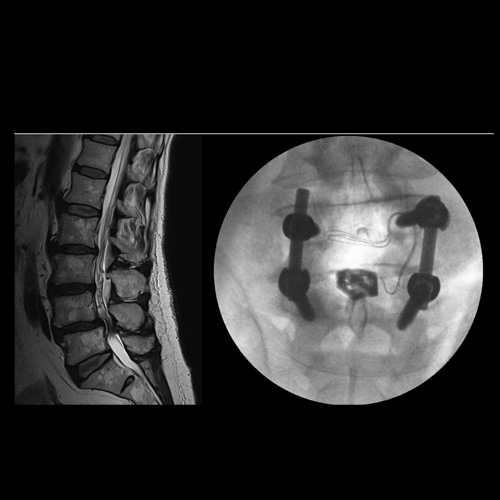

Spinal stenosis (Lumbar) Spinal stenosis (Cervical) Spinal stenosis (Thoracic) Lumbar Disc Herniation Spondylolisthesis Cervical Foraminal Stenosis Vertebroplasty Lumbar Fusion Anterior Cervical Fusion (ACDF) Posterior Cervical Fusion Thoracic Fusion Revision Lumbar Fusion Surgery Facet Joint Cyst Spinal Tumour Minimally Invasive Lumbar Fusion (XLIF) Minimally Invasive Lumbar Fusion (ALIF) Lumbar Fusion (TLIF) Thoraco-lumbar Fusion Lumbar Corpectomy Complex Lumbar Spine Surgery (Spino-pelvic fixation) Complex Cervical Spine Surgery Complex Thoracic Spine Surgery Occipito-cervical Fusion Minimally invasive surgery for thoracic disc herniation Other Related Topics